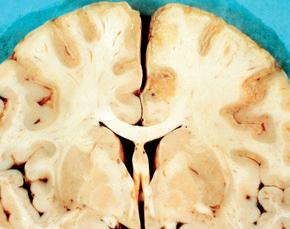

Corte coronal a través de los ganglios basales del cerebro de un niño con encefalitis por sarampión.